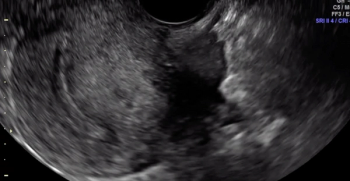

The uterine fundus is being pushed cephalad by the transvaginal ultrasound probe, eliciting smooth sliding of the uterine fundus over the bowel. Some fluid is noted within the rectouterine pouch, which often suggests a non-obliterated pouch.

In this case, there is a fixed ovary posteriorly and subtle hypoechoic nodule posterior to the uterus at the level of the internal cervical os, suggesting of deep endometriosis of the torus uterinus.